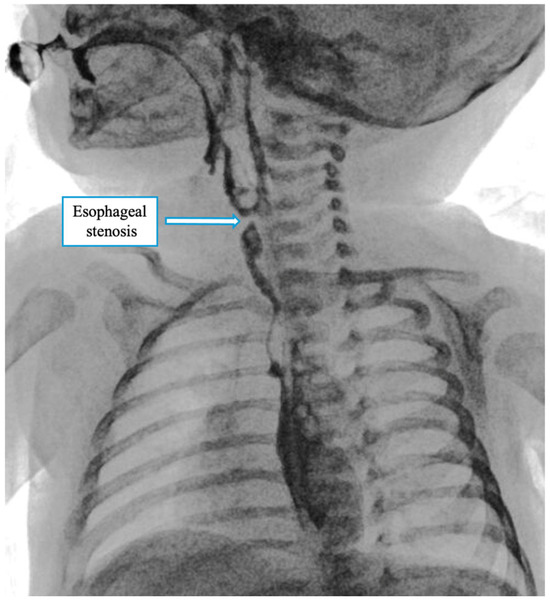

At birth, the baby presented with excessive salivation. Attempts to pass a nasogastric (NG) tube were unsuccessful beyond 9 cm at the lips, indicating an obstruction. The tube was left in place at that level, and a babygram obtained with gentle downward pressure showed the tube coiled in the upper mediastinum and absence of intra-abdominal gas, consistent with esophageal atresia type A (Figure 1).

Figure 1. The esophageal gap and the X-ray showing the replogle tube in the neck and the absence of intra-abdominal gas.